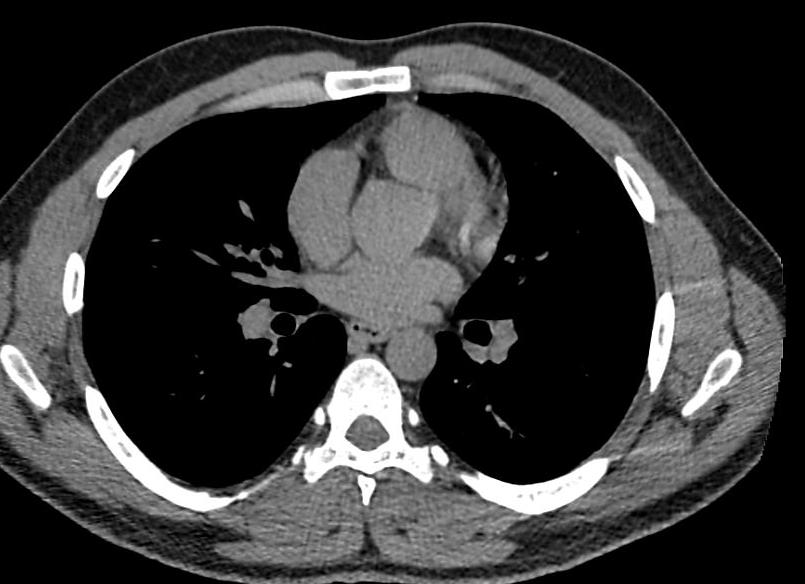

КТ средостения – послойное рентгеновское сканирование медиастинального пространства, обладающее высокой разрешающей способностью и возможностью построения трехмерных реконструкций КТ-изображений. Зона исследования охватывает трахею, пищевод, тимус, сердце, плечеголовные вены, часть верхней полой вены, дугу и нисходящий отдел грудной аорты, легочные артерии и вены, лимфатический проток и лимфоузлы, нервные стволы и сплетения. КТ средостения назначается при подозрении на первичное опухолевое образование или метастазы в органы средостения, саркоидоз, лимфогранулематоз, медиастинит, повреждения грудного протока и т. д. При необходимости более тщательного исследования лимфатических узлов или объемных образований средостения исследование проводится с внутривенным болюсным контрастированием.

В данном клиническом случае сканирование было проведено с контрастомс целью установить вероятный опухолевый процесс. Как и при обследовании других областей тела, при выявлении опухолей средостения всегда используют внутривенное усиление. Атипичные клетки отличаются высокой интенсивностью обменных процессов, и потому активно задерживают контраст, обнаруживая себя таким образом на снимках. Также усиление потребуется при изучении лимфоузлов, особенно если процедура будет проводиться с целью выявления регионарных или отдаленных метастазов рака.

КТ средостения: методика проведения, показания

Сканирование при КТ средостения может выполняться как в пошаговом, так и в спиральном режиме. Оптимальная толщина среза при этом 1,25-2,5 мм, реконструкции по 0,625-1,0 мм выполняются в мягкотканом и костном режиме. При использовании протоколов, подразумевающих контрастирование, ROIвыставляется на дугу аорты, сканирование начинается по достижении плотности крови в аорте 100…120 единиц Хаунсфилда.

Компьютерная томография средостения назначается при: выявлении расширения тени средостения на рентгенограммах с целью уточнить наличие объемного процесса; расширении корней легких (с целью визуализации лимфатических узлов, их картирования и маркирования, а также поиска наиболее подходящих для биопсии лимфоузлов).

В верхнем средостении наиболее часто выявляются опухоли щитовидной железы, а также зобы; в верхнем переднем средостении – опухоли тимуса (тимома) и тератомы; в нижнем переднем средостении – липомы и целомические кисты. В заднем средостении чаще всего выявляются невриномы. Также могут быть выявлены лимфомы.